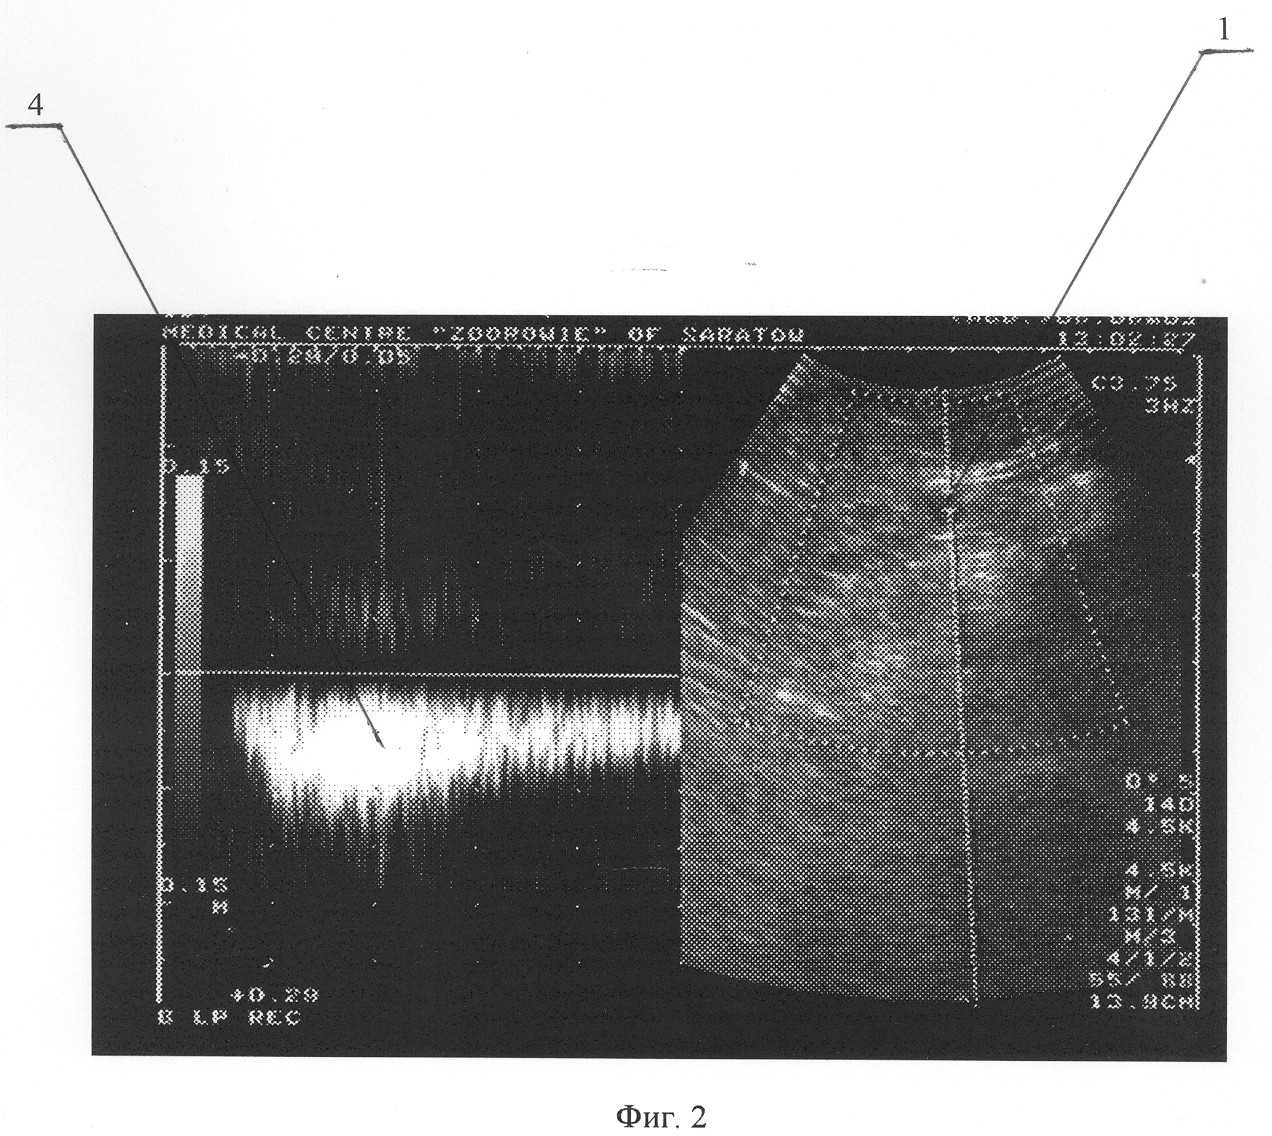

Больному выполнена операция – стволовая катетерная склеротерапия большой подкожной вены на правой голени до уровня коленного сустава. Описание операции: под местной анестезией разрезом длиной 1 см кпереди от медиальной лодыжки выделен начальный отдел большой подкожной вены, вена пересечена, дистальный конец перевязан, в проксимальный конец заведен катетер до уровня коленного сустава. После форсированного введения по катетеру изотонического раствора хлорида натрия и с помощью интраоперационного ультразвукового дуплексного ангиосканирования констатировано интравенозное расположение катетера. После предварительного наложения марлевых валиков по ходу большой подкожной вены и бинтования конечности эластическим бинтом средней степени растяжимости при медленной обратной тракции катетера по нему введено 4 мл 1% раствора фибро-вейна. Рана послойно ушита. Продолжительность операции составила 20 минут. Сразу после операции больной непрерывно ходил в течение 2 часов. Приступил к работе на второй день. Контрольное ультразвуковое дуплексное ангиосканирование произведено на 14 день после операции. Отмечена облитерация большой подкожной вены справа на голени. По стволу большой подкожной вены на бедре – признаки антеградного кровотока. Патологических венозных сбросов не выявлено. На фиг.3 и 4 представлены результаты ультразвукового дуплексного ангиосканирования большой подкожной вены в верхней трети бедра в ортостазе на 14 день после операции; на фиг.3 – во время проведения дистальной компрессионной пробы, на фиг.4 – во время выполнения пробы Вальсальвы, где 1 – просвет большой подкожной вены, 2 – антеградный кровоток по большой подкожной вене при компрессии икроножных мышц; ретроградного кровотока при декомпрессии икроножных мышц, а также при выполнении пробы Вальсальвы не отмечается.